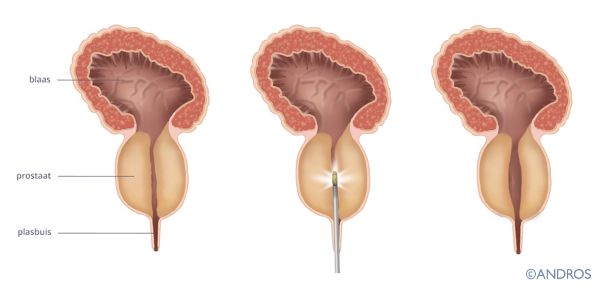

De prostaat ligt onder de blaas, met de plasbuis er dwars doorheen. Naarmate de leeftijd stijgt, wordt de prostaat steeds groter. Daardoor kan de plasbuis in de knel komen. Mannen krijgen dan klachten zoals bijvoorbeeld heel vaak moeten plassen of moeilijk kunnen plassen.

Bij een Rezum behandeling wordt via de plasbuis de prostaat met stoominjecties behandeld. Door de verhitting sterft het behandelde prostaatweefsel af. De prostaat wordt kleiner waardoor er weer beter geplast kan worden. Deze behandeling wordt al zo’n vijf jaar in de VS toegepast.